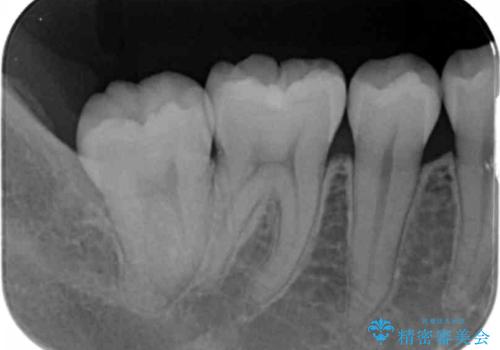

- 奥歯の黒ずみが気になるとのことで来院されました。

樹脂での治療も考えましたが、材料の劣化を避けるためにセラミックインレーでの治療をすることとなりました。

- 右下7 セラミックインレー 77,000円費用は治療当時の料金となります